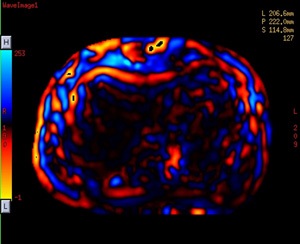

MR-Touch is a Phase Contrast (PC) application that generates an image contrast related to the shear stiffness of soft tissue. MR-Touch is a single touch application that sensitively images the propagation characteristics of acoustic shear waves generated in the tissue of interest. A liver exam is an example of where the application is used.

MR-Touch is performed by synchronizing the Gradient Echo (1.5T pulse sequence used) used with acoustic waves that are applied with an external MR-Touch Device. The pulse sequence is modified with an oscillating Motion Encoding Gradient (MEG). The external acoustic driver is triggered by the PSD so that the MEG is synchronized with the external acoustic wave. The duration of the MEG is the same as the period of the mechanical vibration. A phase shift occurs in the MR signal, which correlates with the mechanical excursion. An algorithm is used to derive a relative stiffness map and wave images from the phase images.

MR-Touch acquisition generates the following image types: magnitude, phase maps, wave maps. Six relative stiffness images are reconstructed for each slice location. The relative stiffness images are reconstructed in color and grey scale, and in masked and un-masked versions. Mask portion is depicted as a checkerboard pattern on the image. It is created to identify regions that should not be included in ROI measurements.